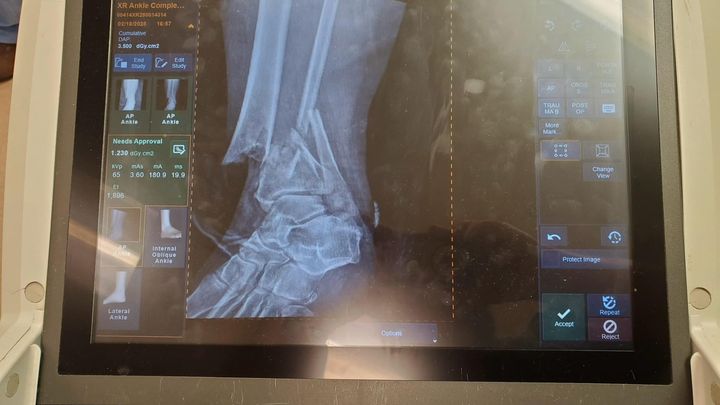

On February 12th, my close friend lost her job. Six days later, she broke her leg in a very, very bad way. She fractured both her tibia and fibula, injured her ankle joint, and the bone broke through the skin. It was a very serious, life-threatening situation. She has been in a trauma hospital to address the severity and set the leg to begin healing, moved to an assisted living facility while waiting for swelling to go down in order to have surgery to add hardware, back to the hospital for said surgery, and now to a rehab center.